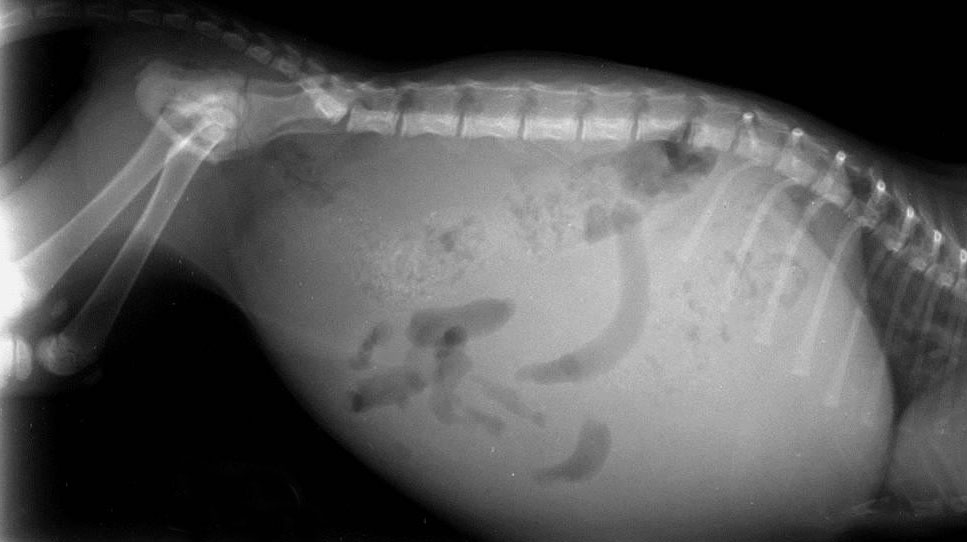

- Отек живота: Живот может быть напряженным и увеличенным в объеме.

Ветеринар проведет тщательный осмотр вашего питомца и назначит необходимые исследования для выявления причины отека. Диагностика может включать:

- Рентген грудной клетки: Помогает оценить состояние сердца и легких.

- УЗИ брюшной полости: Позволяет оценить состояние внутренних органов.